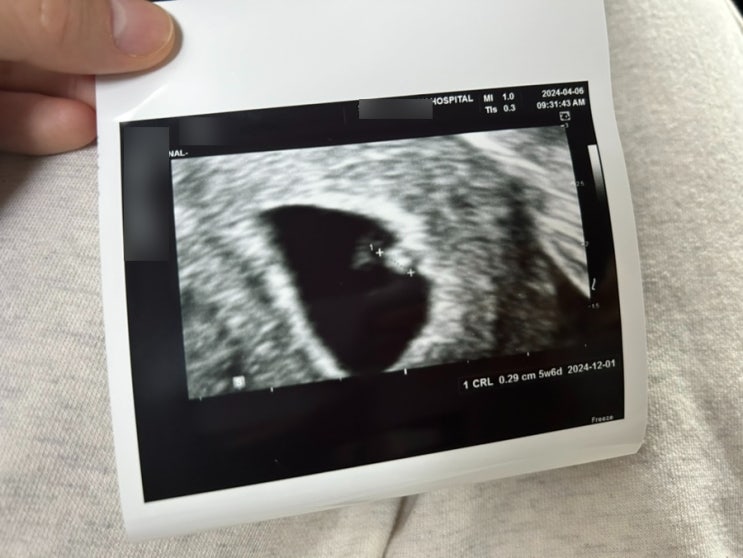

올해가 가기 전에 한번쯤 써보고 싶었던 임신 기록. 생애 마지막 임신과 출산이었기에, 훗날 기억이 흐릿해...